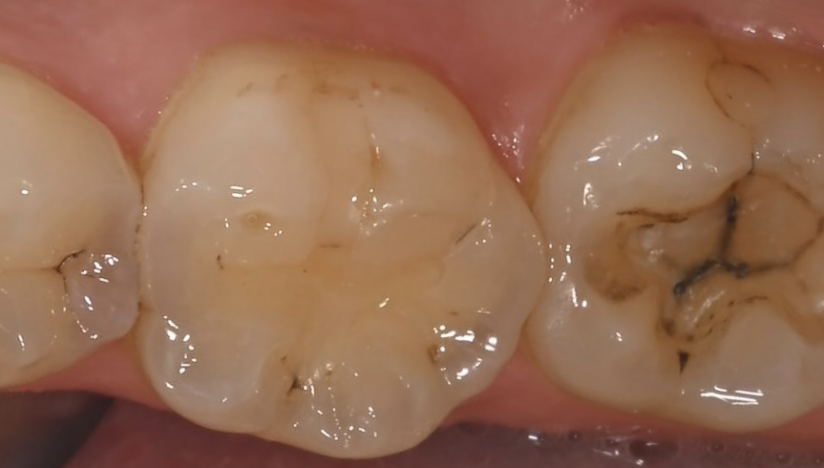

Before

After

主訴

ものが詰まって、染みるようになった。

治療内容

ダイレクトレストレーション2本

治療期間

通院回数1回

治療費用

110,000

治療の

リスク

術後に一時的な知覚過敏症状が出る可能性があります。